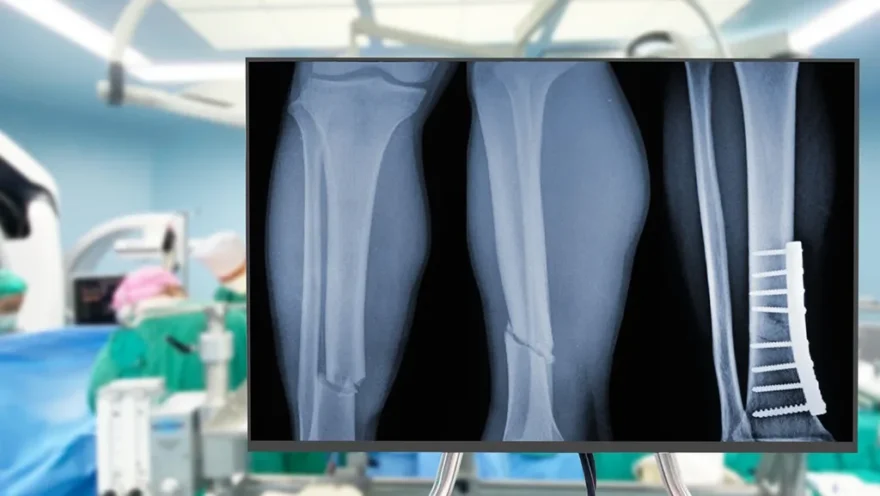

El adhesivo, denominado Bone 02, utiliza una tecnología inspirada en las propiedades de adherencia de las ostras. Su aplicación resulta mínimamente invasiva, requiriendo únicamente una incisión de 2 a 3 centímetros para inyectar el material que une los fragmentos óseos.

Este nuevo procedimiento representa un avance significativo al ofrecer una alternativa a los métodos tradicionales, que usualmente implican el uso de placas y tornillos de metal para la recuperación de huesos.